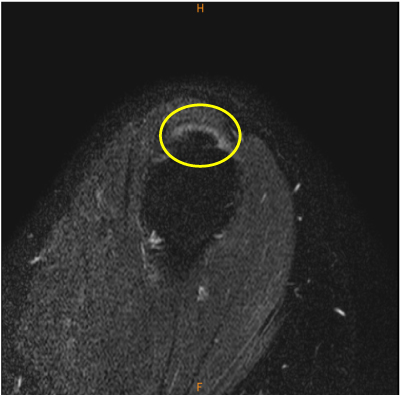

MRI所見

陳旧性石灰沈着性腱板炎のために肩峰下の擦れを生じていると考えられる症例。

石灰沈着は脂肪抑制T2, T2*

画像で気がつきやすい。

診断

陳旧性石灰沈着性腱板炎、擦れ、断裂(-)